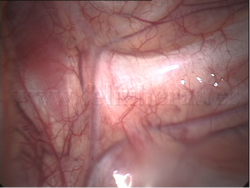

Simpatectomía torácica